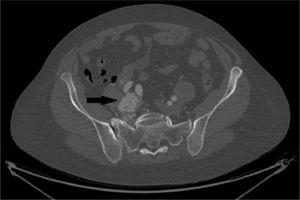

Mujer de 59 años, con antecedente de hipertensión arterial, que en estudio por policitemia se diagnostica mediante una ecografía casual la existencia de trombosis de VCI. No presenta edema de extremidades inferiores. Se completa estudio con angio-TC toraco-abdominal observando trombosis de las venas ilíacas y VCI que se extiende hasta la aurícula derecha. Se inicia tratamiento anticoagulante, y mediante resonancia magnética (RM) pélvica se identifica, además, la existencia de una masa sólida con límites bien definidos adyacente al cuerpo uterino (fig. 1). Ante la sospecha de tumor ginecológico que invade la VCI se solicitan marcadores tumorales que resultan negativos, y se inicia tratamiento con un modulador selectivo de los receptores de progesterona (acetato de ulipristal 5mg/24h). Al mes presenta empeoramiento clínico progresivo con disnea a grandes esfuerzos. El ecocardiograma muestra imagen ecogénica móvil en la aurícula derecha sin afectación valvular. El caso es valorado por un comité multidisciplinario indicando tratamiento quirúrgico.